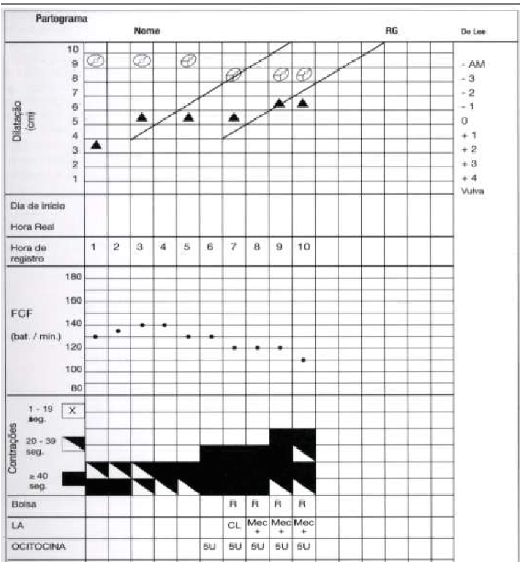

Analise o partograma a seguir e indique o diagnóstico e a conduta obstétrica ideal: